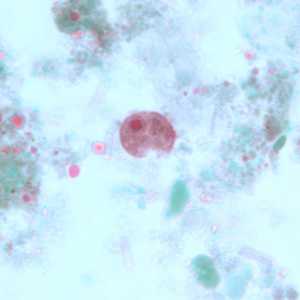

E. coli cysts stained with trichrome.

Figure A: Immature cyst of E. coli, stained with trichrome. Notice the presence of only two nuclei, and a large glycogen vacuole.

Figure B: Mature cyst of E. coli, stained with trichrome. Five nuclei are visible in this focal plane.

Figure C: Mature cyst of E. coli, stained with trichrome. In this specimen, at least five nuclei are visible in the shown focal plane.

Figure D: Mature cyst of E. coli, stained with trichrome. In this specimen, at least five nuclei are visible in the shown focal plane.

Figure E: Mature cyst of E. coli, stained with trichrome. This figure and Figure F represent the same cyst shown in two different focal planes. Eight nuclei can be seen between the two focal planes. Also, above the cyst in this figure, a trophozoite of Endolimax nana can be seen.

Figure F: Mature cyst of E. coli, stained with trichrome. This figure and Figure E represent the same cyst shown in two different focal planes. Eight nuclei can be seen between the two focal planes.